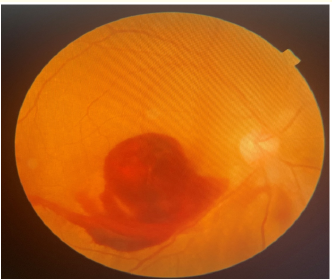

Retinal Vein Occlusion: Epidemiological, Clinical and Therapeutic Aspects at the CADES/O

Baldé Abdoul Karim, Baldé AI, Maxim DS, Houssou MD, Bah TM, Diané S, Ly M, Kolié D and Daddy U. 14(8): 01-09.